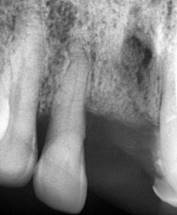

El paciente no refiere odontalgia, por lo que se presenta aparentemente asintomático al examen clínico. Dentro de las pruebas complementarias, se realizó la toma de una radiografía panorámica, donde se evidencio sobras radiolúcidas compatibles con reabsorción de la cresta ósea alveolar con patrón horizontal y vertical generalizado, también se visualizan sombras radiolúcidas alrededor de las raíces de las unidades dentales 1.2, 2.1 y 2.3, compatibles con procesos infecciosos y ensanchamiento del ligamento periodontal; además en la pieza 1.2 se complementó con una radiografía periapical en donde se observa una sombra radiopaca a nivel del tercio apical en el conducto radicular lo que podría indicar una posible calcificación y una sombra radiolúcida que rodea la raíz dental compatible con el posible ensanchamiento del ligamento periodontal; razón por la cual existe movilidad y menor soporte (Figura 2).

Figura 2. Radiografía panorámica y periapical de la pieza N.º 1.2

Elaboración: Los autores.

Para establecer el diagnóstico periodontal los valores obtenidos de la profundidad del sondaje, margen gingival, nivel de inserción, movilidad y línea mucogingival ayudaron a determinar que el paciente presenta periodontitis crónica severa generalizada según la clasificación de 1999 y endodónticamente al realizar pruebas de vitalidad a la pieza dental 1.2. Se presentó ausencia de respuesta lo que indica necrosis pulpar y periodontitis apical asintomática, de acuerdo a estos diagnósticos se le manifestó al paciente un plan de tratamiento basado en primera instancia la realización de una profilaxis, seguido de un raspado y alisado radicular con el fin de realizar una profunda eliminación de la placa alojada y mejorar el estado periodontal, el cual fue aprobado por el paciente. Posteriormente se evaluó la pieza 1.2, donde se determinó su extracción, ya que no fue posible realizar una endodoncia por el estado de afección y calcificación del conducto radicular, asimismo, el grado de comprometimiento del tejido periodontal avanzado, dando un pronóstico desfavorable. Se llevaron a cabo dos citas, en la primera se realizó una profilaxis, posteriormente raspado y alisado radicular.